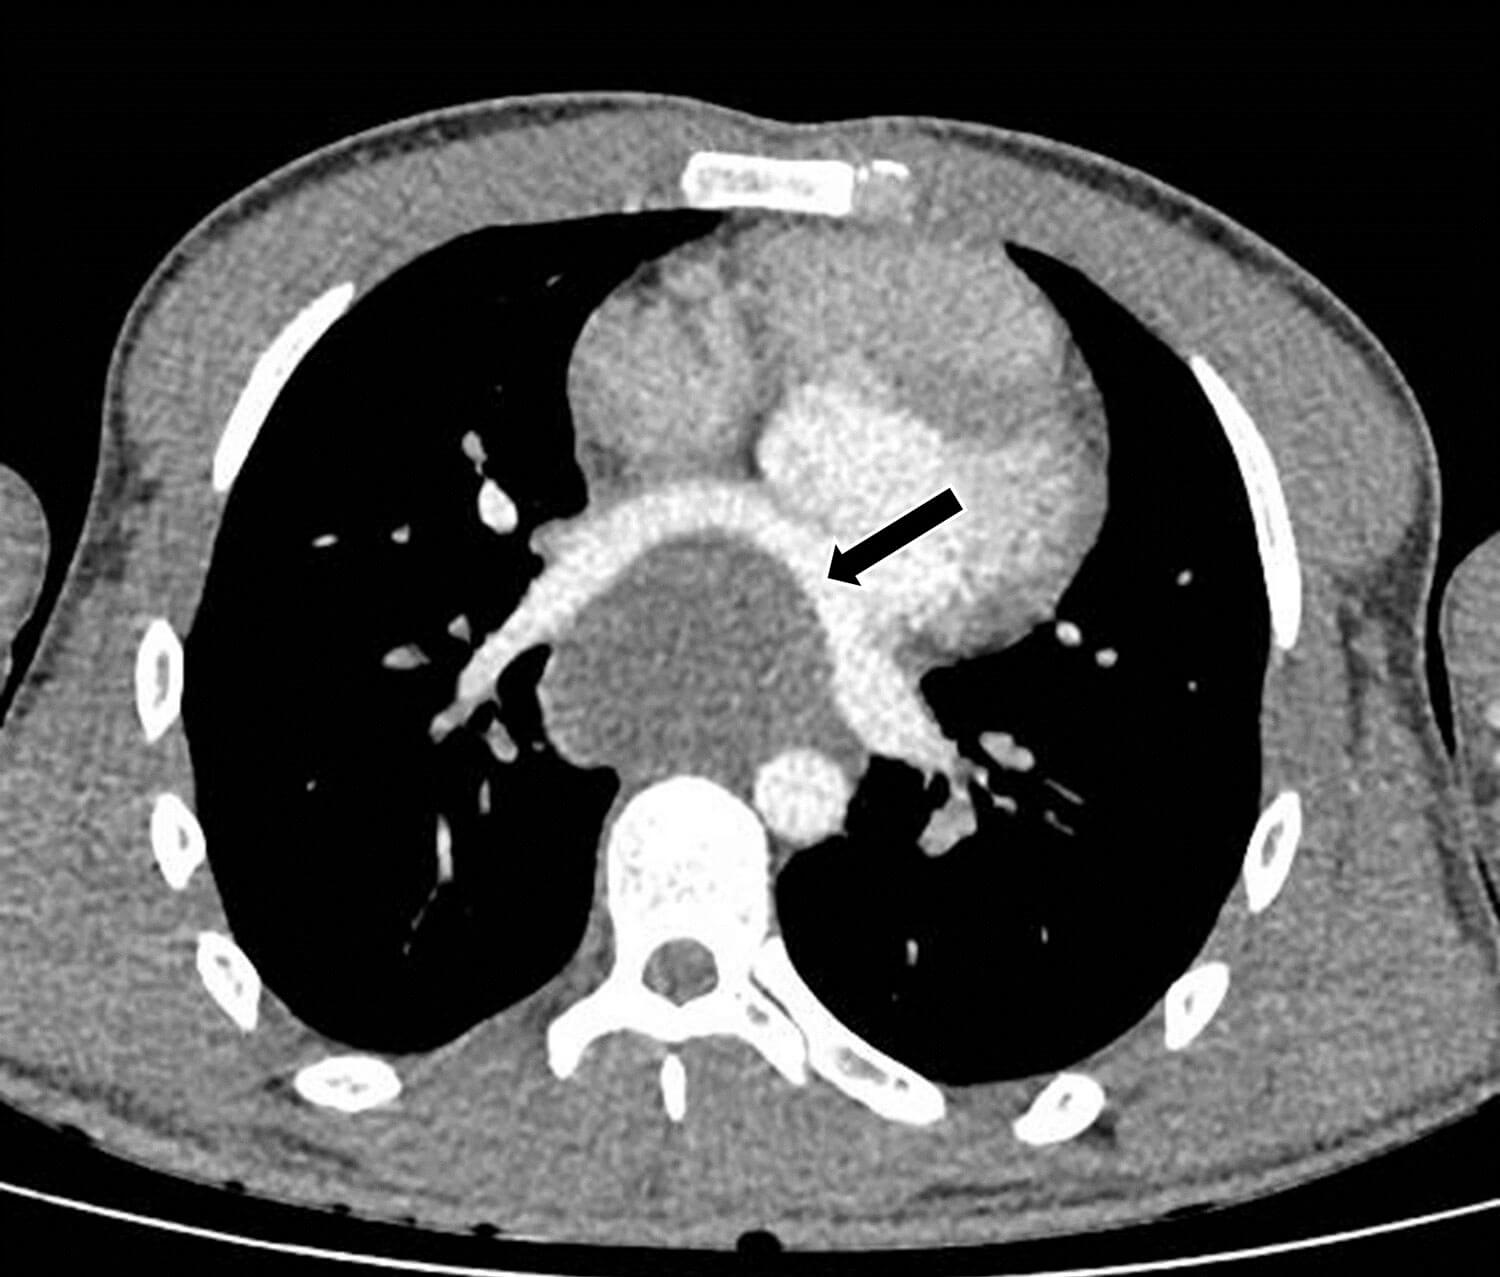

A 23-year-old man presented to A&E with sudden onset chest pain, hypotension and tachycardia. A chest x-ray was suggestive of a mass posterior to the heart, and a bedside echocardiogram was suspicious for an atrial mass measuring 6 x 6cm. The patient was reviewed by both the cardiology and respiratory teams. A CT and MRI thorax showed a large mediastinal mass compressing the left atrium, but the aetiology was inconclusive with differentials including a benign bronchogenic cyst (Figure 4). Imaging surveillance was recommended and the patient was discharged home.

Figure 4: 7 x 5 x 7cm low attenuation mediastinal mass compressing the left atrium.

He represented five months later when he collapsed at home with seizures and a reduced Glasgow Coma Scale (GCS). On further questioning, he reported headaches for the past 11 weeks and poor vision from his left eye. An MRI brain showed a haemorrhagic lesion in the occipital lobe and multiple ring-enhancing lesions in the cerebrum and cerebellum suspicious for brain metastases (Figure 5).

Figure 5: Haemorrhagic lesion in the right occipital lobe and ring enhancing lesion in the cerebellum, suspicious for metastases.

A repeat CT chest, abdomen and pelvis redemonstrated the large mediastinal mass, unchanged in size, but with new mediastinal lymphadenopathy and bilateral pulmonary metastases. Lymph node biopsy concluded choriocarcinoma as final histology. Testicular examination and ultrasound were highly suspicious for right testicular malignancy. The patient was urgently transferred to a specialist trophoblastic disease centre for inpatient chemotherapy.